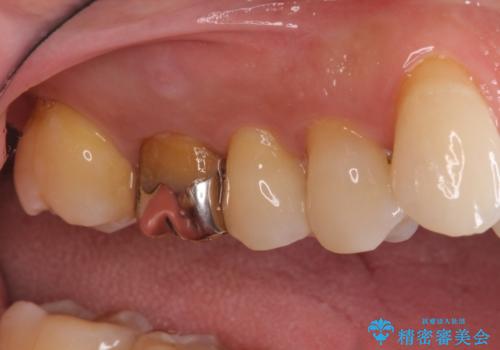

- 2年ほど放置していた左上の仮歯がとれたことをきっかけにご来院された患者様です。

セラミック治療がご希望でしたが、ときどき歯肉が腫れるということで根管治療もご希望されました。

左上の仮歯を2年使用して穴があいて外れたことをきっかけにご来院されました。

レントゲン上からも、歯の中(根管)が汚れている可能性があることをご説明したところ、根管治療からやり直しをすることになりました。